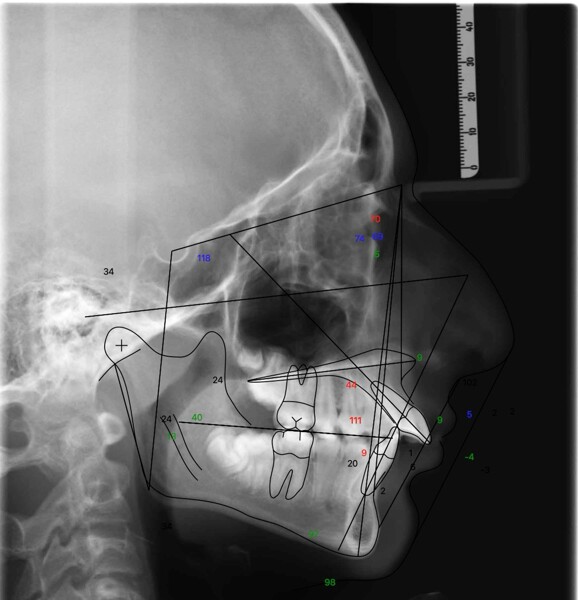

Fig. 4: Pretreatment cephalometric tracing superimposed on the lateral cephalogram.

Cephalometric analysis confirmed a Class II skeletal pattern primarily caused by mandibular retrusion (ANB = 5°; SNB = 69°) and showed reduced mandibular length (94 mm versus a norm of approximately 110 mm; Fig. 4; Table 1). The vertical pattern was normo-divergent (SN/GoGn = 34°). Dentoalveolar analysis showed severe maxillary incisor proclination, pronounced crowding in both arches and an accentuated curve of Spee. Soft tissue analysis showed lower lip entrapment associated with the increased overjet, contributing to an unfavourable facial profile.

Table 1: Initial cephalometric analysis showing sagittal, vertical, basal and dental measurements compared with reference norms.